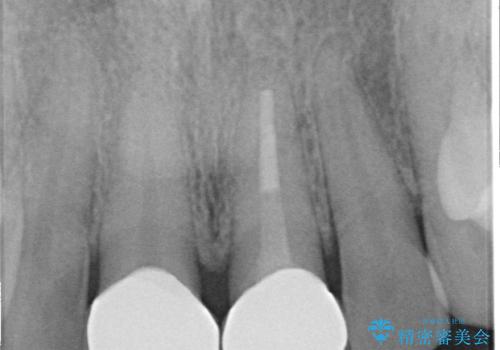

- 前歯の変色が気になるのでセラミックによる治療を行いたいといらっしゃった方の症例です。

左上1番目の歯の再根管治療終了後、左右1番目の2歯をオールセラミッククラウンで補綴しました。